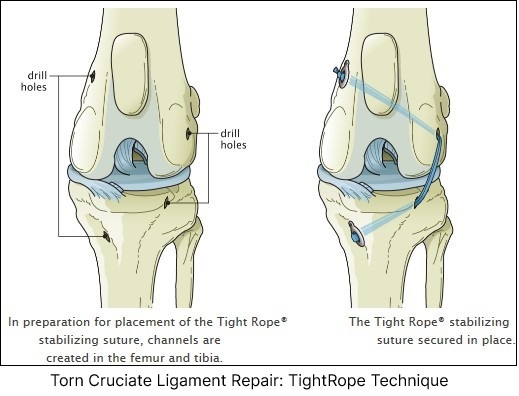

What Tightrope CCL Procedure for Torn ACL?

The Tight Rope Procedure is a variation of the lateral suture procedure.

Uses high-strength fiber implants to reinforce joint stability.

Less invasive alternative to TPLO and TTA.

Suitable for dogs with mild to moderate instability.

Advantages:

The suture material is anchored at more isometric points, allowing for a more natural range of motion while maintaining stifle stability.

Provides superior stabilization compared to traditional extracapsular techniques.

Minimally invasive compared to osteotomy-based techniques.

Disadvantages:

The use of a large, braided suture significantly increases the risk of serious infection.

Requires precise surgical technique and specialized equipment.